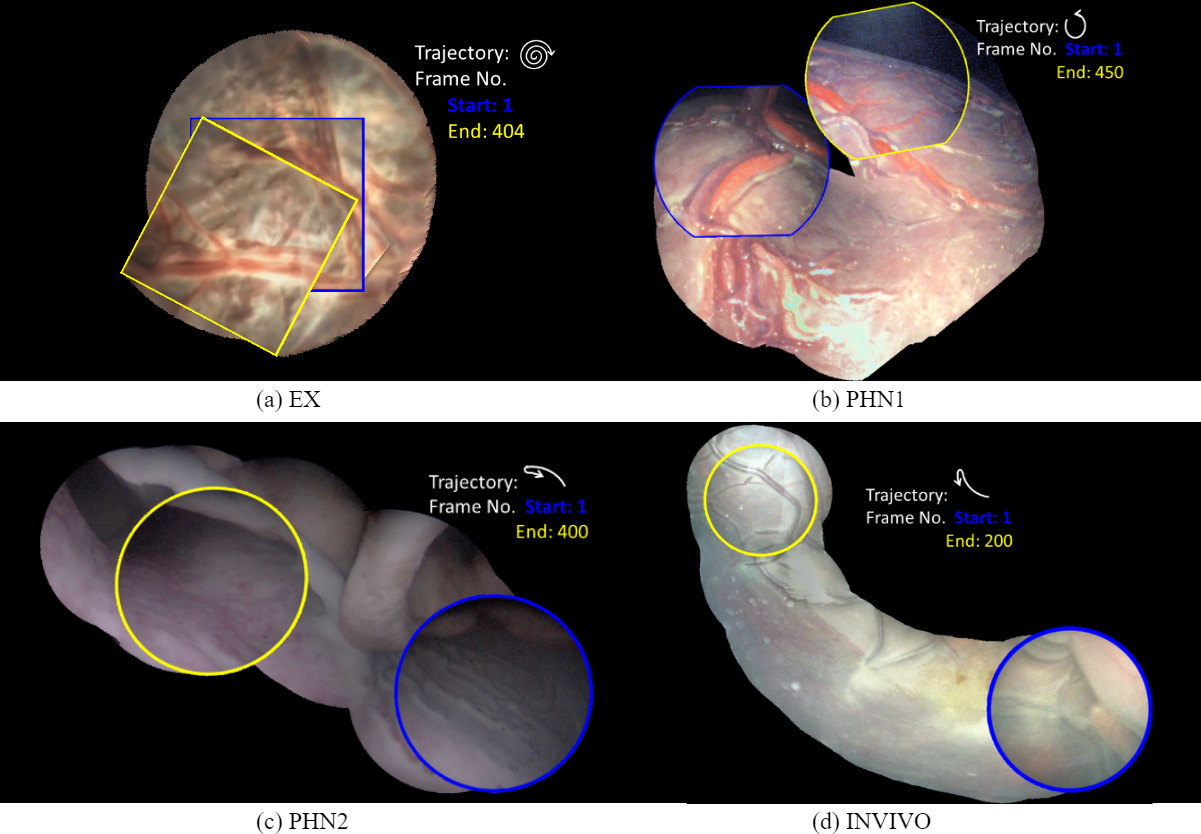

Mosaics generated using the proposed DSM for the EX, PHN1, PHN2 and INVI sequences are shown in Fig. 5. These mosaics are best assessed in the supplemental video that shows the qualitative comparison with respect to FEAT and DIH. DSM created a meaningful mosaic for EX (unseen data) with minimum drift accumulation over time which can be observed from the start and end frames in Fig. 5(a). PHN1 contained non-planar views without occlusions with a freehand circular trajectory. DSM generated reliable mosaics with minimum drift (Fig. 5(b)), however FEAT drifted away due to non-planar views, insufficient feature matches and long-range videos. PHN2 and INVI represent the most challenging scenarios containing highly non-planar views with heavy occlusions, low resolution and texture paucity. We observe from Fig. 5(c)(d) that although the generated mosaics can serve well for increasing the FoV, yet there is a noticeable drift due to highly challenging conditions. Such errors may be corrected by end-to-end training using the photometric loss [8].

Refer to caption

Figure 5: Qualitative results of the proposed DSM on four diverse fetoscopic videos. The motion trajectories, start and end frames are marked for visualization.